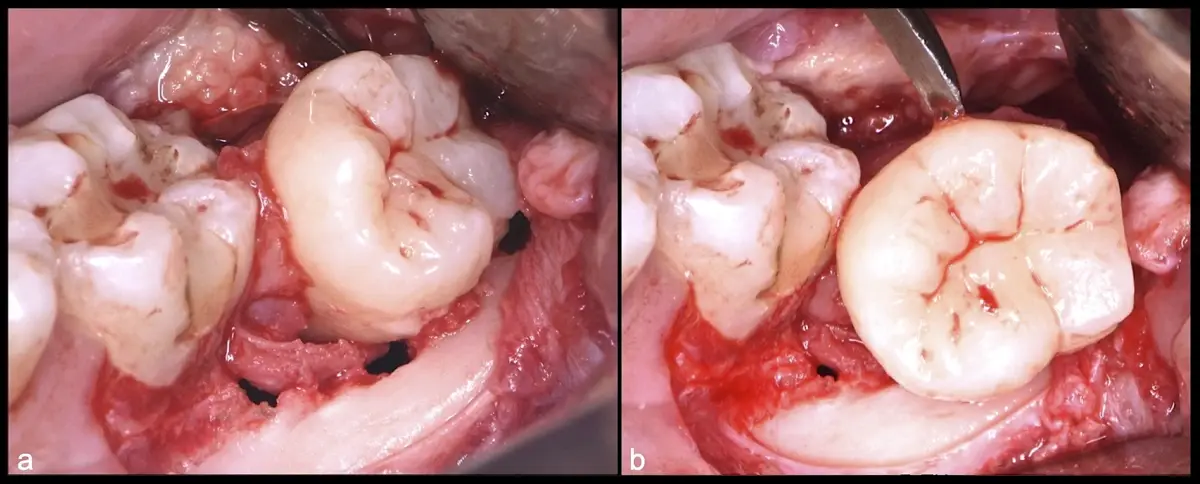

El procedimiento puede variar en su complejidad dependiendo de su ubicación, profundidad, angulación, y la densidad ósea circundante.2 Uno de los pasos más críticos y cruciales en la extracción es la osteotomía previa y concomitante al acceso quirúrgico del diente, para lo cual se utilizan diversos instrumentos como cinceles y martillos, instrumental rotatorio o de corte por ultrasonido.3

Para realizar la técnica de extracción de una tercera molar, una vez que se ha confirmado su diagnóstico, se debe considerar la posición del diente (vertical, mesioangular, distoangular, horizontal u otras), profundidad y grado de impacto, obstrucción a la erupción asociada a la segunda molar, morfología de la raíz (la curvatura de las raíces controla el camino de la exodoncia), relación con el canal del conducto dentario inferior, la patología asociada, la densidad ósea y la Integridad de la segunda molar.

El procedimiento se inicia colocando anestesia troncular para bloqueo del nervio dentario inferior y sus ramas. Luego, se establecerá el diseño de acceso según la disposición de la molar a extraer. Para fines didácticos, se explicará cómo se realizaría la extracción de la molar de la Figura 1: se realiza una incisión horizontal a nivel de la zona retromolar hasta llegar a distal de la segunda molar, continuándose con una incisión intrasurcular hasta mesial de la segunda molar, finalizando con una incisión vertical a espesor total hasta llegar a la línea mucogingival (Figura 2).